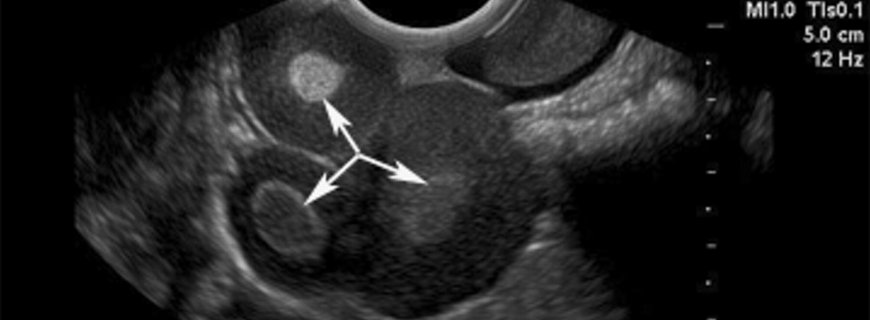

Erişkin tipi (olguların %95\'i) çoğunlukla menopoz sonrası kadınlarda görülmektedir. Çocukluk tipi (%5) 30 yaşın altındaki hastalarda ortaya çıkmaktadır. Granüloza hücreli tümör olgularında muayene esnasında içi dolu veya kistik lezyon net olarak ele gelmektedir. Bu hastalarda sıklıkla karında genişleme ve rahatsızlık yakınmaları görülmektedir. Hastaların yaklaşık %10\'unda kitlenin boyutları arttığından ve karında sıvı biriktiğinden karın belirtileri görülmektedir. Kitlenin giderek büyümesi karın ağrısı, idrarda yanma, sık idrara çıkma ve kabızlık gibi komşu organlara bası etkisi ile oluşan yakınmalara yol açabilir.

Granüloza hücreli tümör şüphesi bulunan hastaların jinekolojik onkoloğa refere edilmesi yararlı olacaktır; menopoz sonrası ve ilk adetten önceki dönemlerinde olan hastalardaki kanser riski daha yüksek olduğundan bu konsültasyon önem taşımaktadır. Radyolojik veya ultrasonografik kanser bulguları taşıyan hastalar (endokrinolojik belirtileri ve kitlesi bulunan hastaların) jinekolojik onkolog ile yapılacak ameliyat öncesi konsültasyondan yarar görecektir. En önemlisi cerrahi tedavidir. Uygun evrelendirme ile birlikte tümörün tam olarak çıkarılması cerrahi tedavinin başlıca amaçlarıdır. Nüks ortalama 5 yıl sonra saptanmakta ve ortalama bir yaşam beklentisi gözlenmektedir, ilerlemiş hastalığı bulunan olgularda kemoterapi ve/veya radyoterapi uygulanabilir.